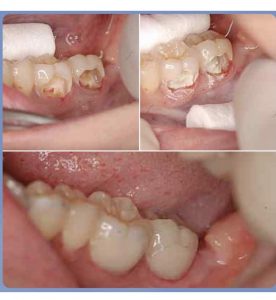

歯髄(歯の神経)をどこまで残せるか

大きく虫歯が進行すると歯の中枢にある歯髄(神経)まで影響を及ぼします。

虫歯が歯髄まで進行すると、歯の神経を取ることに。

歯の状態にもよりますが、すでに汚染された必要最低限の神経のみを取り除き、そこにMTAセメントというケイ酸3カルシウム主成分の材料を使って歯の神経を保存出来る場合があります。